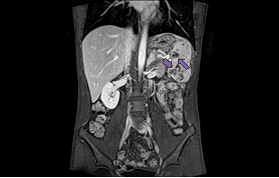

Later CT abdomen done showed multiple hypodense lesions of varying sizes are noted in the spleen; some of the lesions appear ill-defined and conglomerate. Multiple sub centimeter and borderline/mildly enlarged retroperitoneal lymph nodes were noted (Figure 1).

Figure 1 Contrast enhanced CT scan of the abdomen acquired in the Porto-venous phase showing multiple irregular ill-defined hypodense splenic lesions of varying sizes.